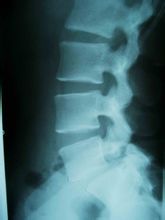

对于腰椎骨质增生,除了X片外,还有一些其他的诊断标准:

6.X片显示椎体有骨赘增生,椎间隙狭窄。